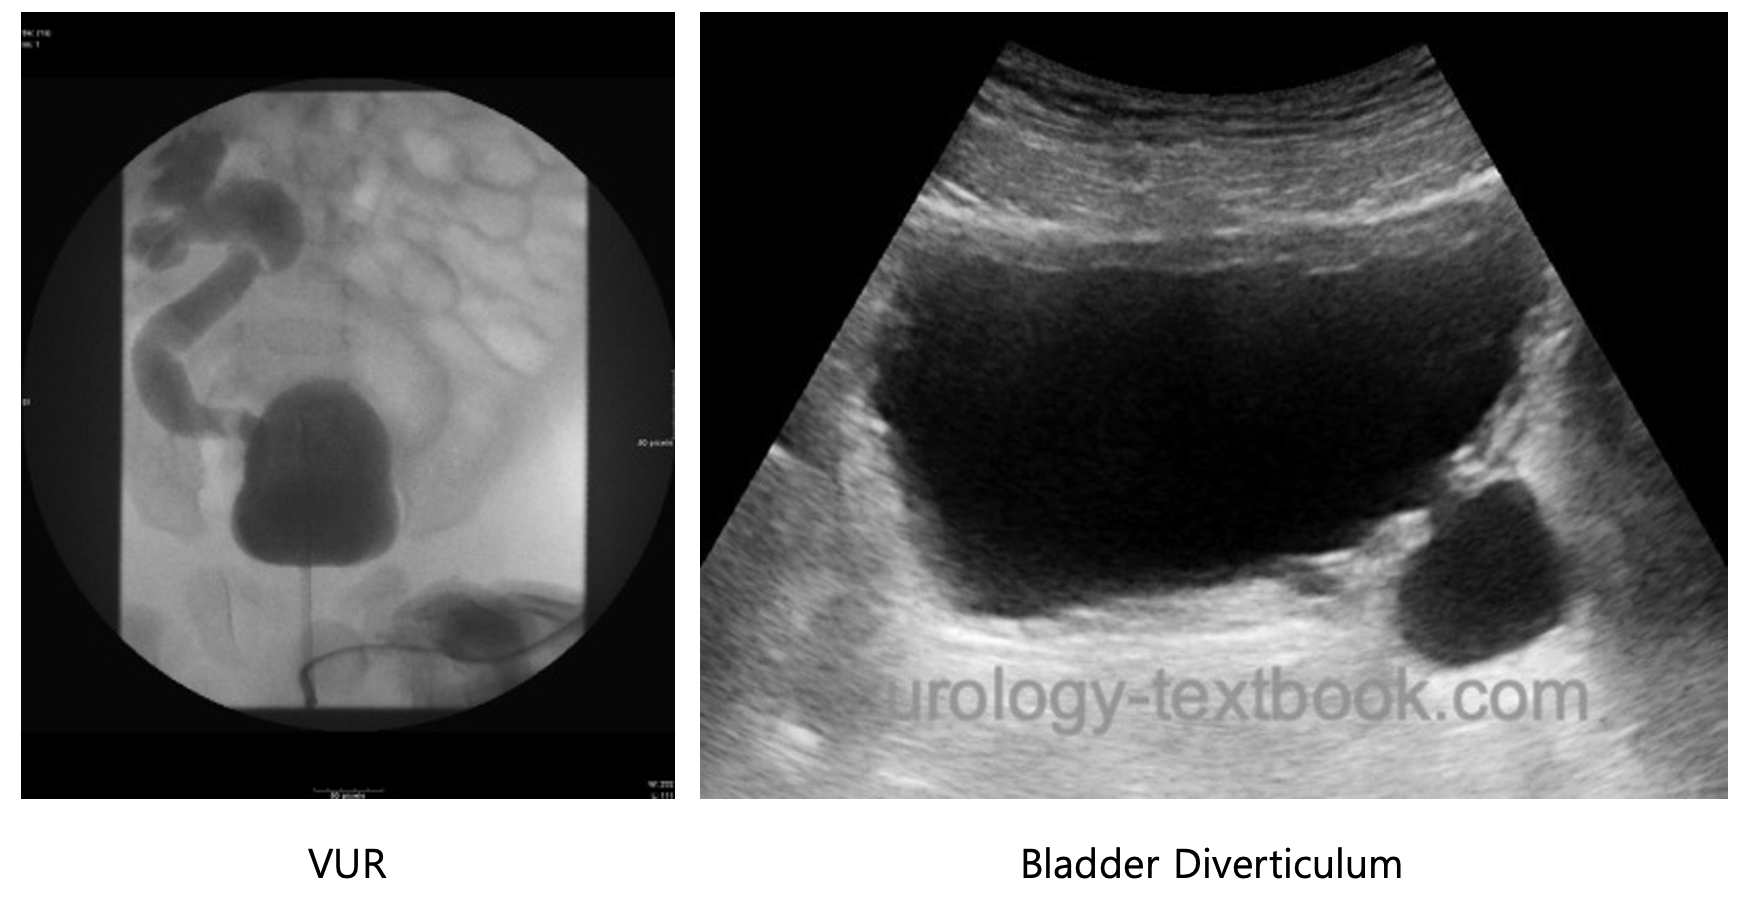

• VUR

• congenital bladder diverticulum